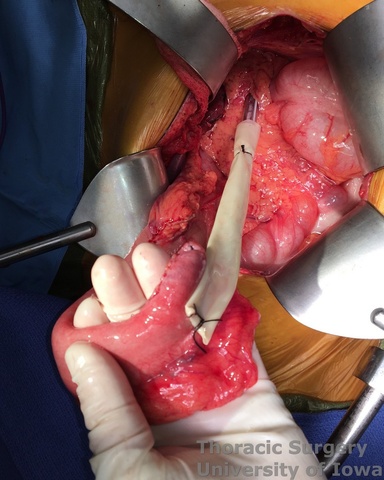

- Through the abdomen, the hiatus is enlarged to allow a hand entry. Circumferential midesophageal and proximal esophageal dissection is gently completed in the superior mediastinum with fingers sequentially through the neck incision (along with gently traction on the cervical esophagus) and hiatus (along with gently traction on the Penrose around the gastroesophageal junction).

- Once the intrathoracic esophagus is mobile, the esophagus is divided with a linear stapler in the neck incision (NG tube is pulled back), preserving as much cervical esophagus as possible (usually 8-10 cm distal to the cricopharyngeus muscle)

- The stomach and lower thoracic esophagus are delivered out of the abdominal incision.

- The mediastinum is inspected for bleeding with the use of the lighted transhiatal retractor. The mediastinum is packed.